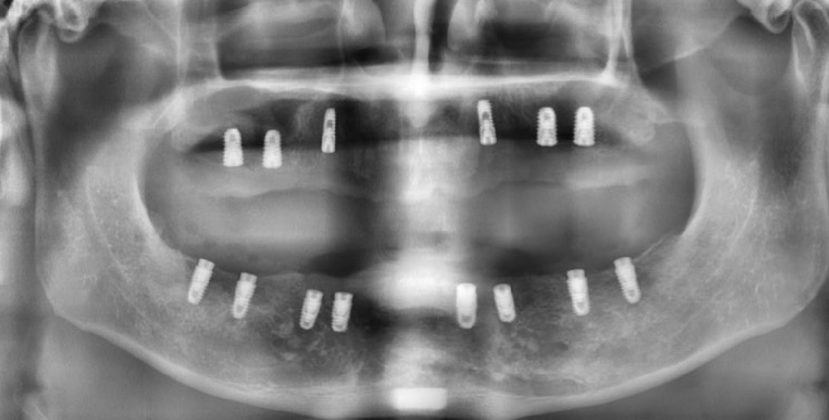

나이가 들면서 전체 치아가 흔들리거나 손상되어 발치 후 전체 임플란트(전악 임플란트)가 필요한 경우가 많아요. 특히 만 65세 이상 환자분들은 평생 1인당 2개까지 임플란트 건강보험 혜택이 적용되니 꼭 확인해 보세요! 이번 증례는 심각한 잇몸 질환으로 모든 치아를 상실한 60대 환자분께서 정교한 맞춤형 전악 임플란트를 통해 건 강한 미소와 저작 기능을 회복한 과정입니다. CASE. 60대 남성 환자, '전체 치아 흔들림'으로 내원 "전체 치아가 흔들리고 아파서 임플란트를 하고 싶어요." 여러 치과를 알아보시던 중, 지인의 소개로 저희 병원을 찾아주셨습니다. 처음부터 전악 임플란트를 염두에 두고, 풍부한 임상 경험을 가진 의료진을 찾고 계셨습니다. 정밀 진단 결과 구강 검진 및 CT 촬영 결과, 환자분의 상태는 매우 심각했습니다. * 구강 상태: 위아래 모든 치아가 심하게 흔들리고, 치아 뿌리가 노출될 정도로 잇몸 조직이 붕괴된 상태였습니다. * CT 및 파노라마 소견: 치아를 지지해야 할 잇몸뼈(치조골)가 염증으로 인해 대부분 소실되어, 치아들이 뼈 속에서 떠 있는 '부유치(floating tooth)' 상태였습니다. 자연치아를 최대한 보존하는 것이 원칙이지만, 이미 치아 뿌리 끝까지 염증이 퍼져 회복이 불가능했습니다. 환자분께 상태를 자세히 설명드린 후, 전체 발치 및 전악 임플란트 계획을 수립했습니다. ![]() ![]() 개인별 맞춤 치료 계획 환자분의 구강 구조와 심미성을 고려하여 아래와 같이 맞춤형 치료 계획을 세웠습니다. * 상악 (윗니): 6개의 임플란트 식립 후 '임플란트 지지 부분틀니 (IARPD)' 붕괴된 앞니 잇몸과 입술의 볼륨감을 심미적으로 회복시키기 위해, 어금니는 임플란트 고정성 보철로 단단히 잡아주고 앞니는 틀니의 잇몸 부분(flange)을 이용해 자연스러운 외모를 재현하는 방식입니다. * 하악 (아랫니): 8개의 임플란트 식립 후 전체 ‘고정성 보철' 전체 치아를 임플란트와 보철물로 단단하게 고정하여 본래 치아처럼 편안하게 사용하는 방식입니다. 치료 과정 1. 발치 및 잇몸 회복 모든 치아를 발치한 후, 염증이 완전히 사라지고 잇몸이 안정될 때까지 약 2개월간 기다렸습니다. 이 기간 동안 환자분의 식사와 심미성을 위해 임시 틀니를 제작해 드렸습니다. ![]() 2. 정확하고 안전한 임플란트 식립 - 상악수술: 잇몸뼈가 얇아 고난도 수술인 상악동 거상술을 동반하여, 계획된 위치에 정확하게 6개의 임플란트를 식립했습니다. 충분한 마취와 정교한 수술, 그리고 숙련된 봉합으로 환자분의 불편감을 최소화하고 빠른 회복을 유도했습니다. ![]() - 하악수술: 최종 보철물의 형태와 기능을 고려하여 적절한 간격과 위치에 8개의 임플란트를 완벽하게 식립했습니다. ![]() 3. 뼈 유착 및 2차 수술 임플란트가 뼈와 단단히 붙는 약 3~4개월 동안 임시 틀니를 사용하며 기다립니다. 이후 모든 임플란트의 ISQ 수치(임플란트 안정성 지수)가 양호한 것을 확인하고, 잇몸 밖으로 임플란트를 노출시키는 간단한 2차 수술을 진행했습니다. ![]() 4. 임시 보철 및 최종 보철 준비 현재는 최종 보철물을 올리기 전, 임시 보철물(PMMA)을 사용하여 환자분이 적응하는 단계를 거치고 있습니다. 임플란트가 완벽하게 식립되었기 때문에 성공적인 최종 결과가 기대됩니다. 전악 임플란트는 단순한 치아 보철을 넘어, 무너진 식생활과 자신감을 회복하는 중요한 치료입니다. 이백점치과는 최소한의 임플란트 식립으로 통증과 불편을 줄이면서도 안정적이고 심미적인 결과를 추구합니다. 풍부한 임상 경험과 높은 환자 만족도로 증명된 실력으로, 치아가 전혀 없는 분들도 다시 편안한 식사와 활짝 웃는삶을 되찾을 수 있습니다. 당신의 현명한 선택, 이백점치과와 함께하세요. |